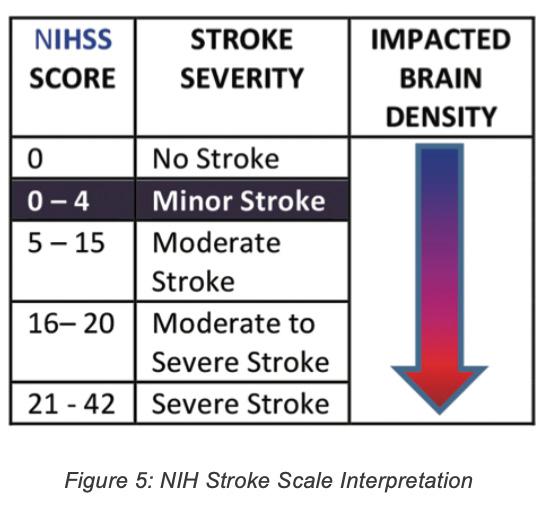

Various stroke screening techniques were used. The results are shown in the following figures:

Pharmacological Therapy: Since the CT showed that the stroke was ischaemic rather than haemorrhagic, pharmacological intervention was indicated rather than a surgical approach.

The patient was outside the therapeutic window for administration of Tissue plasminogen activator (tPA) which is 3-4.5 hours, and was therefore started on aspirin 75mg daily, Dipyridamole 100mg tds and Simvastatin 20mg daily. The patient was also started on omeprazole 20mg once daily due to the potential side effect of gastrointestinal bleeding associated with aspirin.